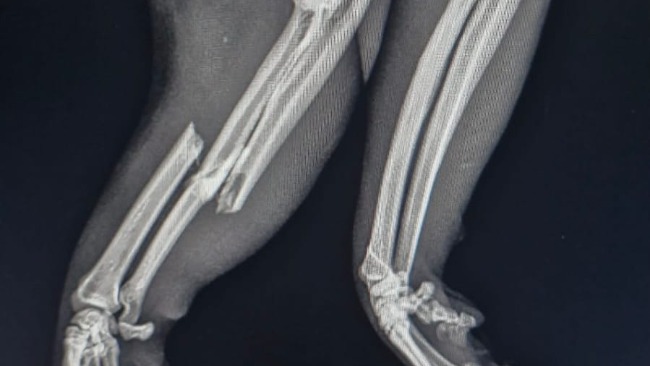

Zdiagnozowano złamanie kości przedramienia prawego i spojenia żuchwy. Usg jamy brzusznej nie wykazało odchyleń od normy. Kot został zabezpieczony przeciwbólowo i czeka na zabieg osteosyntezy.